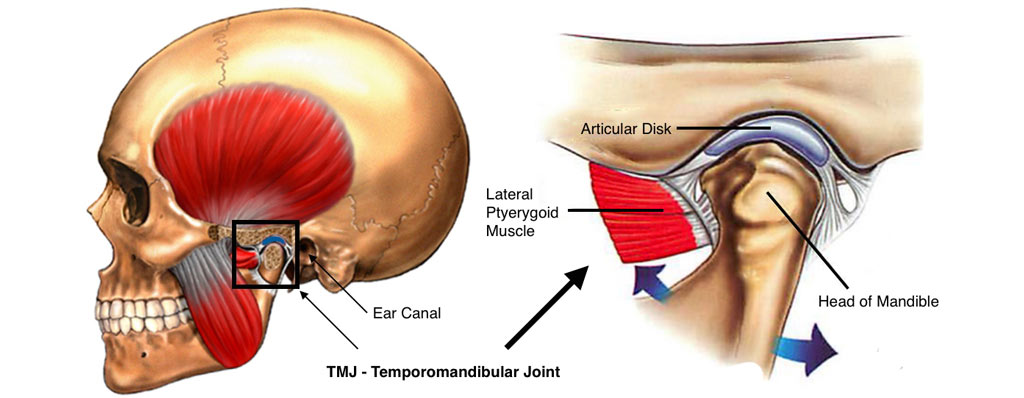

Temporomandibular joint disorders should be treated with proper care for the patients. Temporomandibular joint disorders can be caused because of different types of causes. Some of the causes include accidents, trauma, idiopathic mistakes done by the dentists or doctors as well as due to several procedures done in relation to the jaws and the bones. The temporomandibular disorders have got several symptoms in several patients. This includes pain or tenderness in your ears, jaws, ears, teeth as well as difficulty in proper and sufficient amount of opening of the mouth. You will have difficulty with the opening of the mouth in a normal way which will hinder in the normal opening of the mouth and difficulty in normal chewing and swallowing of the foods. Moreover, it is important to realize the symptoms at the right point of time to ensure that the dentists can help you to get the right treatment do for yourself.

Tmj anklosys leading to deficient mandible and deficient chin corrected by TMJ Surgery followed by Orthognathic surgery